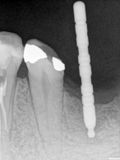

fredlibc | all galleries >> Galleries >> WYu - 36 implant > R1.jpg

R1.jpg